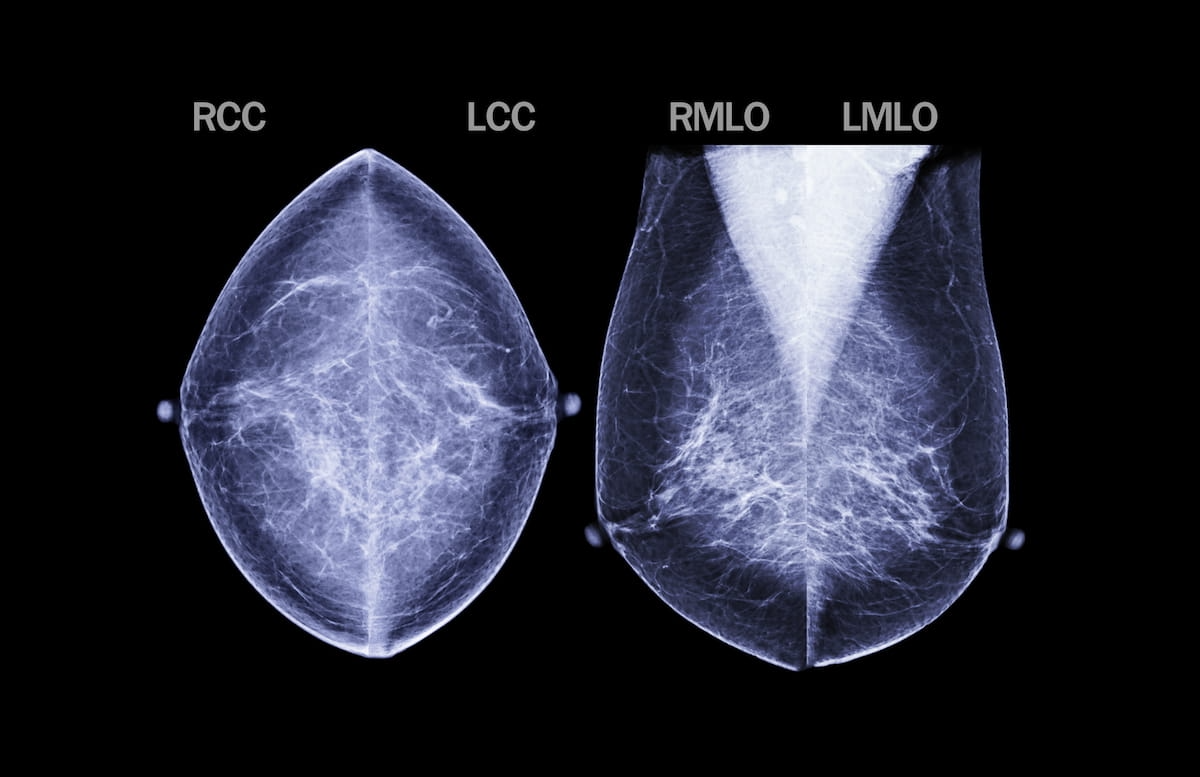

Preoperative MRIs should be done on all newly diagnosed breast cancer patients, regardless of breast density.

Preoperative MRIs should be done on all newly diagnosed breast cancer patients, regardless of breast density, say researchers from Yale University School of Medicine in New Haven. The results of their study were presented at the American Roentgen Ray Society Annual Meeting in Vancouver, Canada.

Preop MRIs are ordered more often for young women or those who have dense breasts, said Reena Vashi, MD, one of the study authors. However, researchers studied 127 patients to determine if 3T MRI could be of use preoperatively in detecting additional malignancies - regardless of age or breast tissue density.

The researchers found that preop MRIs detected additional malignancies in 26 percent of patients whose breasts were not considered dense and in 25 percent of patients with dense breast tissue. There were no differences between the groups regarding the sizes or distribution of the lesions.